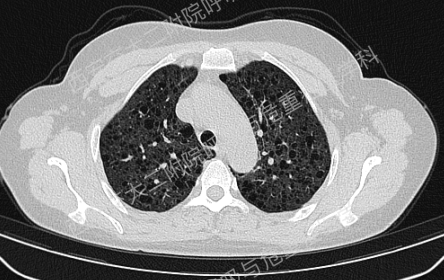

上图所示肺部多发囊性病变,双肺广泛分布,直径在2-10mm之间,壁薄,囊壁间组织相对正常。结合育龄期女性等临床资料,不难诊断淋巴管平滑肌瘤病(LAM)。对疑似LAM的女性的初步评估还应包括血管平滑肌脂肪瘤的筛查、淋巴管受累以及是否存在未被诊断的结节性硬化症。该例患者经评估后诊断散发型S-LAM。

该患者肺功能下降达到治疗标准,但患者及家属暂不考虑用药,选择观察,目前随访中。曾咨询乘飞机到拉萨的问题,鉴于症状稳定,可乘坐飞机,但不建议上高原。